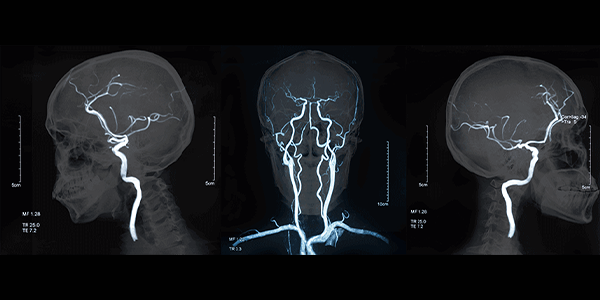

Beyin anjiyosu, beyindeki kan damarlarını detaylı olarak görüntülemek için kullanılan genel bir tanısal görüntüleme yöntemidir. Bu işlemde, kontrast madde verilerek röntgen veya floroskopi altında beyin damarları görselleştirilir.

BiPlan anjiyografi ise, beyin anjiyosunun daha gelişmiş bir versiyonudur. Temel fark, görüntülerin alınma şeklindedir:

• Geleneksel (Tek Plan) Beyin Anjiyosu: Görüntüler tek bir açıdan alınır. Bu, damarların iki boyutlu bir görüntüsünü sağlar.

• BiPlan Anjiyografi: Aynı anda iki farklı açıdan görüntü almak için özel bir röntgen cihazı kullanılır. Genellikle bu açılar dik açılardadır. Örneğin, ön-arka ve yan açıları kullanılır.

Beyin_Anjiyografisi_e2bbe7ef.webp

A Life Sağlık Grubu olarak, beyin ve damar hastalıklarının teşhis ve tedavisinde BiPlan Anjiyografi sistemini kullanıyoruz. Bu teknoloji ile sizlere yüksek kaliteli sağlık hizmeti sunmaktan gurur duyuyoruz.

• Yüksek Çözünürlüklü ve Detaylı Görüntüleme: BiPlan teknolojisi, en küçük damar anormalliklerini yüksek çözünürlükte görüntüler. Bu sayede doğru teşhis konulabilir.

• Hızlı ve Etkili İşlem: Eş zamanlı iki farklı planda görüntüleme sayesinde, işlem süresi kısalır ve hastanın maruz kaldığı radyasyon miktarı potansiyel olarak azalır.